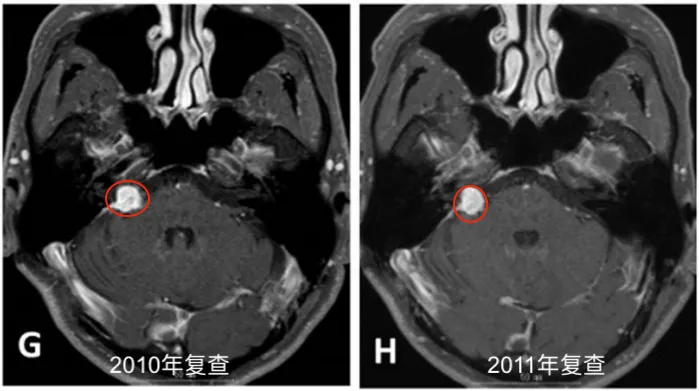

2004年4月初始MRI显示右侧桥小脑角区肿瘤不均匀强化。2005年8月首次术后、伽玛刀治疗前影像资料记录肿瘤状态。2007年5月第二次术前MRI评估显示肿瘤进展,术后一个月影像确认切除范围。

定期随访影像资料(图1 E-J)完整记录2008-2013年肿瘤变化情况。2013年末至2014年初复查显示肿瘤再次生长,2014年4月术前MRI显示肿瘤不均匀强化伴脑干受压。术后两个月随访影像确认次全切除结果。